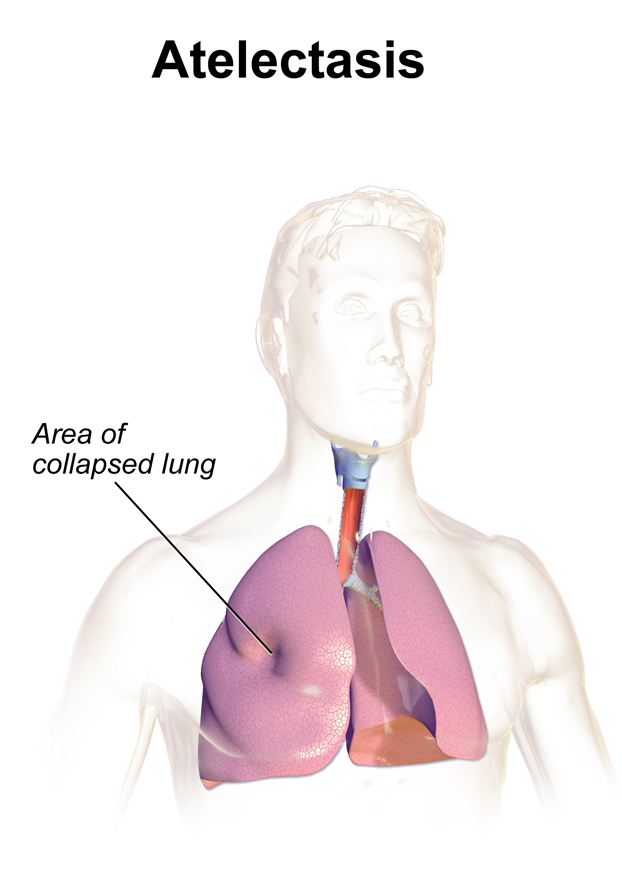

Fundamentally, atelectasis refers to the collapse of the lung parenchyma WITH the qualifier that the visceral and parietal pleura remain attached. This is different from other types of lung collapse such as pneumothorax (where air enters between the parietal and visceral pleura, separating them).

- Opacity/increased signal: collapse of the lung parenchyma will increase the density in the affected area, resulting in an opacity on a chest X-ray (or increased signal on other studies).

- Shift of mediastinal structures TOWARD the atelectasis: given that the parietal and visceral pleura remain intact with one another, the vacuum from the collapse will pull nearby structures toward the atelectasis.